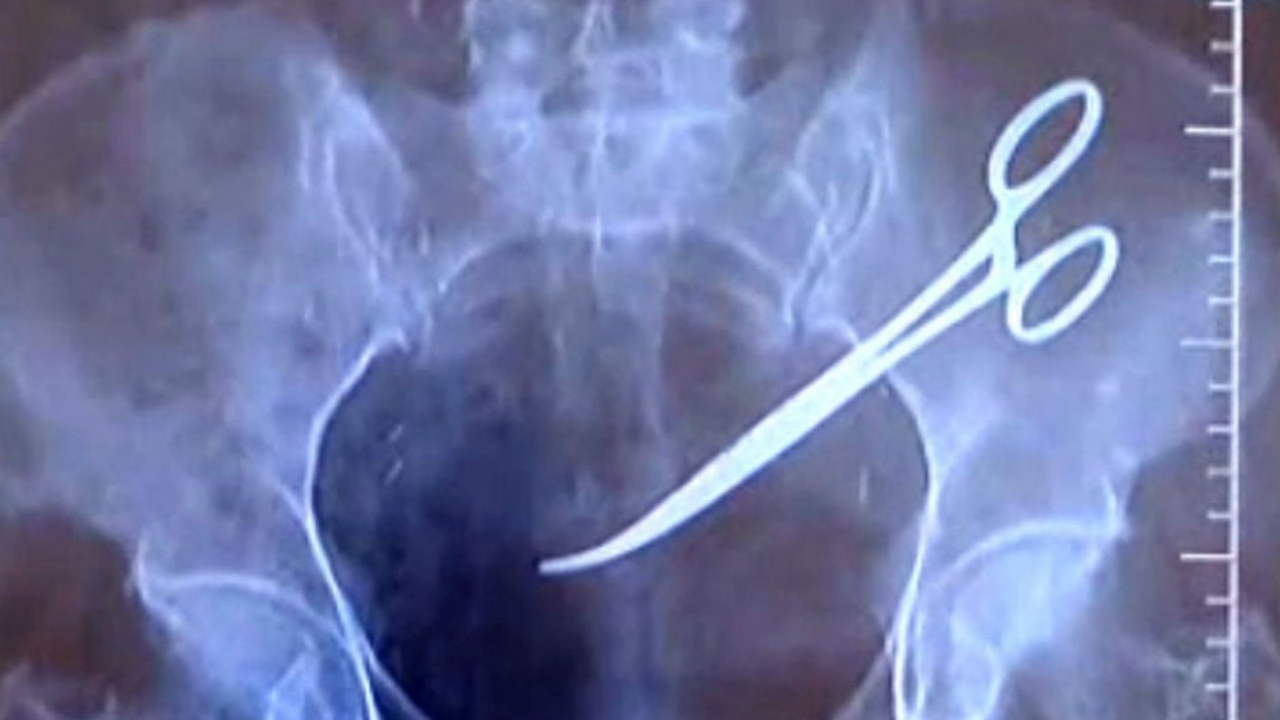

Antes de iniciar cualquier denuncia, es fundamental determinar si realmente se trató de negligencia médica. Esto ocurre cuando un profesional de la salud actúa con imprudencia, descuido o falta de pericia, causando daño al paciente. Algunos ejemplos incluyen:

- Errores durante cirugías o procedimientos médicos.